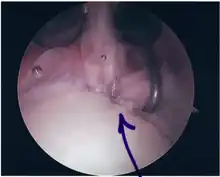

Surgical treatment of SLAP tears has become more common in recent years. The success rate for repairing isolated SLAP tears is reported between 74-94%.[8] While surgery can be performed as a traditional open procedure, an arthroscopic technique[9] is currently favored being less intrusive with low chance of iatrogenic infection.[10]

Following inspection and determination of the extent of injury, the basic labrum repair is as follows.

- The glenoid and labrum are roughened to increase contact surface area and promote re-growth.

- Locations for the bone anchors are selected based on number and severity of tear. A severe tear involving both SLAP and Bankart lesions may require seven anchors. Simple tears may only require one.

- The glenoid is drilled for the anchor implantation.

- Anchors are inserted in the glenoid.

- The suture component of the implant is tied through the labrum and knotted such that the labrum is in tight contact with the glenoid surface.